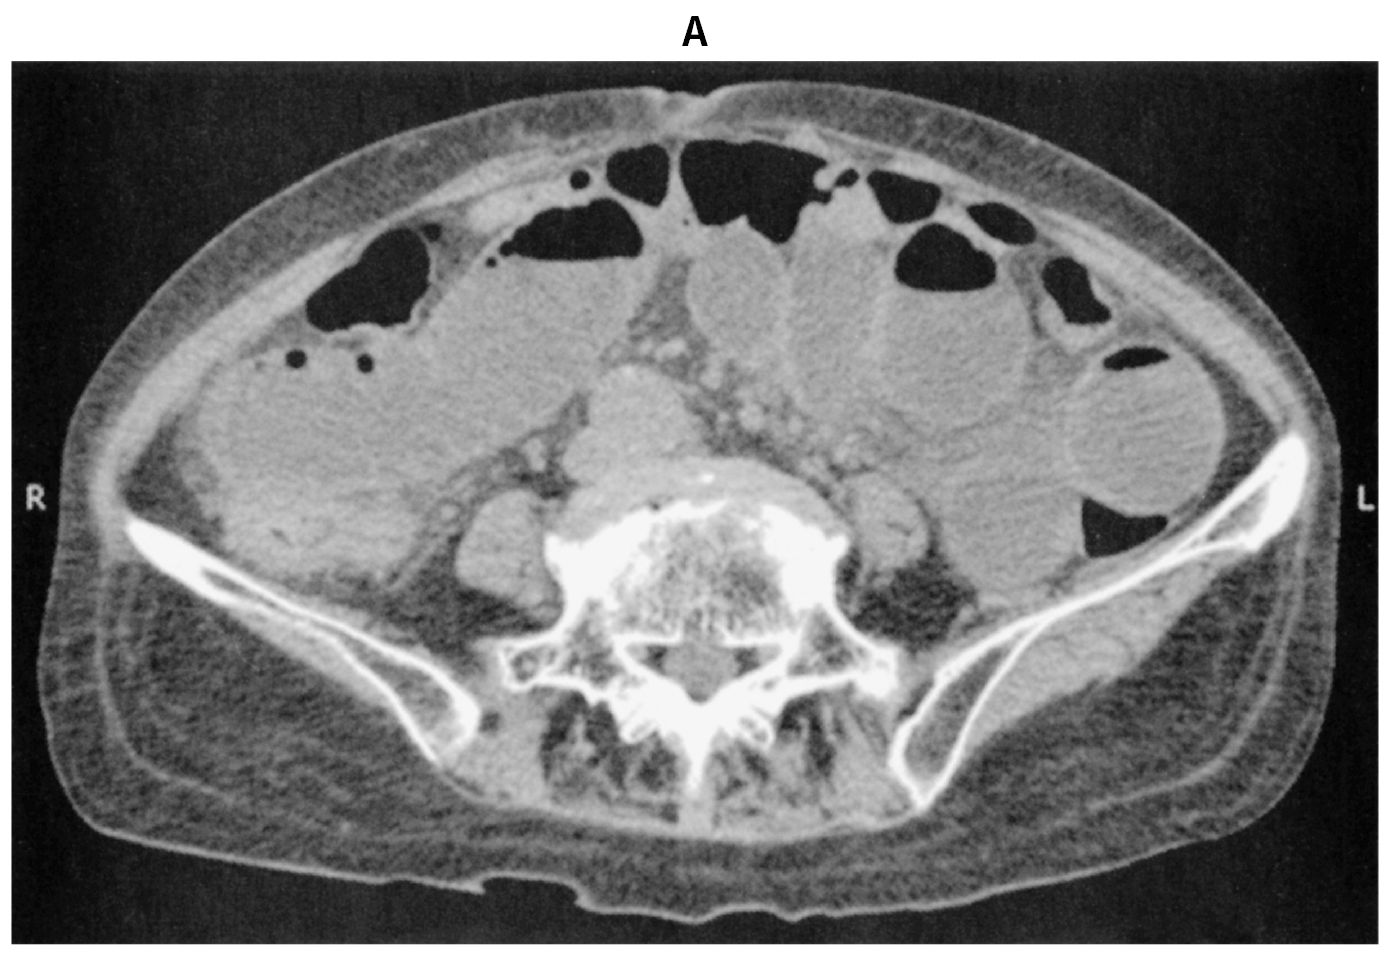

75歳の女性。腹痛と嘔吐を主訴に来院した。2日前から排便と排ガスがなく,徐々に腹部膨満が出現してきた。今朝から腹痛と嘔吐が出現したため受診した。既往歴は骨粗鬆症で治療中である。3年前に子宮筋腫で子宮全摘術を受けた。喫煙は20本/日を30年間。飲酒は日本酒1合/日を30年間。意識は清明。身長160cm,体重75kg。体温36.9℃。脈拍112/分,整。血圧148/74mmHg。SpO2 97%(room air)。①腹部膨隆を認める②腹部全体に軽度の圧痛を認めるが,③反跳痛を認めない④筋性防御を認めない⑤左股関節の伸展,外転により下肢の痛みやしびれを認める。直腸指診で異常を認めない。血液所見:赤血球410万,Hb 13.0g/dL,Ht 40%,白血球9,600,血小板27万。血液生化学所見:総蛋白6.4g/dL,アルブミン3.0g/dL,AST 25U/L,ALT 15U/L,尿素窒素35mg/dL,クレアチニン1.0mg/dL。CRP 2.5mg/dL。腹部単純CT(A)(B)を下に示す。

下線部のうち,この患者の腸閉塞の原因に特徴的な所見はどれか。